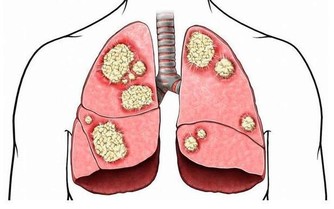

鼻子不靈,同時經常咳嗽,有時甚至呼吸困難,這是肺功能逐步衰退的標誌。病人首先要注意飲食,戒菸或者控制吸煙量,也不要和經常吸煙的人在一起。多吃新鮮瓜果和蔬菜,加強體質鍛煉,防止肺部合併症的發生。